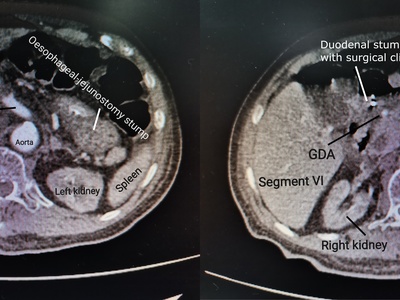

Gastrectomy (Partial/Total)

Removal of part or all of the stomach for cancer, severe ulcers, or bleeding conditions.